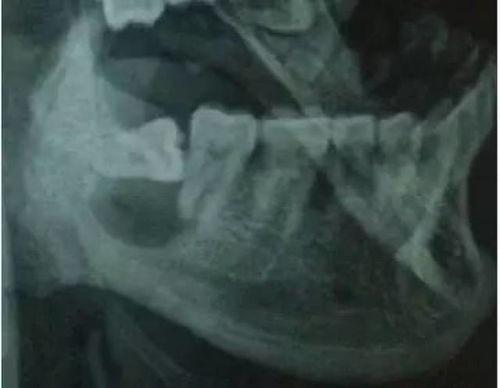

在正式进入手术室之前,你可能会在网络上看到很多关于拔智齿前的准备工作。首先,医生会给你做全面的口腔检查,确保你的智齿位置合适,拔除难度不大。他们会给你讲解手术过程,让你对即将发生的事情有个大致的了解。

别急,让我带你一探究竟。在拔智齿的视频中,你可以看到医生们是如何使用专业的工具,小心翼翼地分离智齿与牙槽骨的连接。他们会用牙挺、牙钳等工具,将智齿从牙槽骨中拔出。整个过程看似简单,但实际上需要医生们丰富的经验和精湛的技艺。